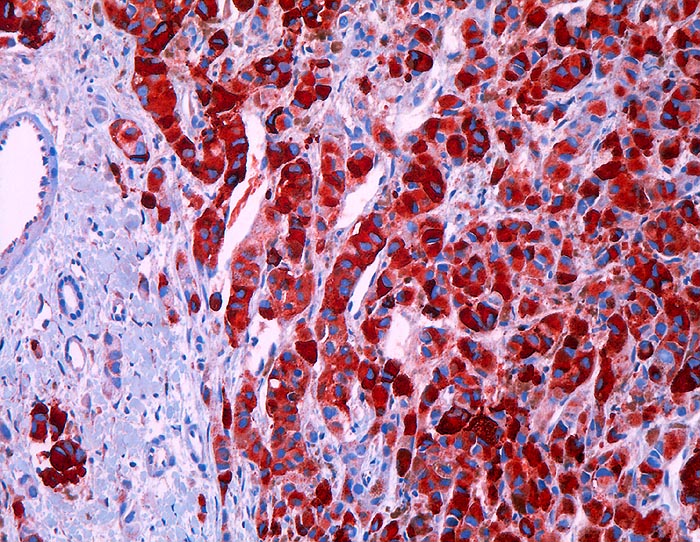

l/ HMB-45

HMB-45

Anfärbung:

Zytoplasma

Reaktion im Normalgewebe:

Aktivierte Melanozyten und Naevi, Mammaepithel und Schweissdrüsenepithel.

Reaktion in Neoplasien:

HMB-45 wird in diversen melanozytären und nicht melanozytären Tumoren exprimiert:

Naevi (meist nur oberflächlich)

Malignes Melanom (90% Primärtumoren, 80% Rezidive und Metastasen, desmoplastische Variante meist negativ)

Angiomyolipom

Lymphangioleiomyomatose

Klarzelltumor der Lunge (Sugar tumor)

Einzelne Mammakarzinome, Speicheldrüsentumoren, Karzinome, multiple Myelome

Diagnostischer Nutzen:

Identifikation der verschiedenen HMB-45 positiven Tumoren.

Spezifität für maligne Melanome höher als S-100, aber niedrigere Sensitivität.